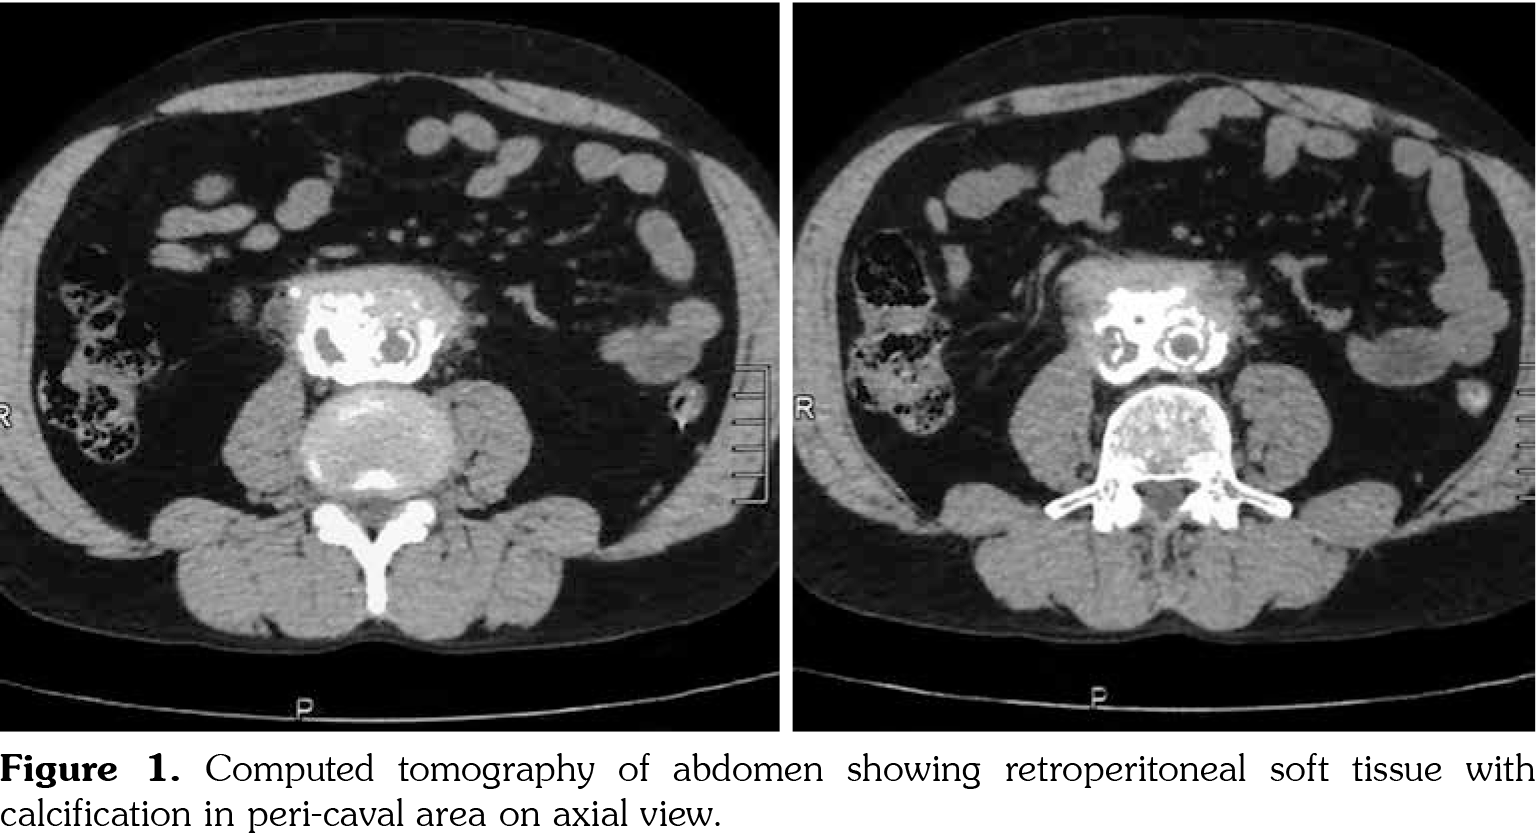

On investigations, his complete blood count was normal. Erythrocyte sedimentation rate was 88 mm in first hour. Random blood sugar was 93 mg/dL. His serum urea was 26 mg/dL and serum creatinine was 1.1 mg/dL. Liver function tests were within normal limits. Chest X-ray revealed non-homogenous opacities in bilateral lung fields. Pulmonary function tests revealed forced expiratory volume in one second (FEV1) of 61% and forced vital capacity (FVC) of 73%. FEV1/FVC ratio was 84%. Two-dimensional echocardiography was within normal limits. Ultrasonography of the abdomen revealed small-sized right kidney (6.9x2.9 cm) with dilated pelvi-calyceal system and dilated proximal ureter. Computed tomography (CT) of the abdomen revealed medial deviation of right ureter and presence of retroperitoneal soft tissue along infra-renal aorta and peri-caval area with calcification extending up to iliac vessels suggestive of RPF (Figures 1, 2, 3, and 4). High-resolution CT of the chest confirmed presence of interstitial lung disease (ILD). ANA profile (ENA) revealed that anti-U1 snRNP was strongly positive. Rest of the autoantibodies were negative. His serum immunoglobulin G levels were within normal limits. Thus, we arrived at a diagnosis of MCTD with RPF and ILD. He was started on mycophenolate 720 mg twice daily, hydroxychloroquine 200 mg once daily and deflazacort 6 mg once daily for MCTD, pirfenidone 400 mg twice daily for ILD and tamoxifen 20 mg once daily for RPF. On follow-up at six months, he was doing physically well. His symptoms of cough were reduced and dyspnea improved from NYHA class IV to class II. Repeat pulmonary function tests revealed FEV1 of 59%, FVC of 71% and FEV1/FVC ratio of 84%. However, repeat ultrasonography of the abdomen did not reveal any significant change in pelvi- calyceal system.

In 1972, Sharp et al.,[1] recorded a group of patients who had clinical features of SLE, SSc and PM with high titers of anti-extractable nuclear antigen antibody. They published it as a new disease entity: MCTD. Since then, there has been an increasing number of classification criteria published for the diagnosis of MCTD, namely, Kasukawa et al.[3] Alarcon-Segovia and Villareal[4] and Kahn and Appelboom.[5] There has been no consensus on clinical features owing to varied manifestations and frequent overlap of symptoms with other autoimmune conditions. However, high titers of antibodies against U1 snRNP have been found in most patients.[6] Our patient had symptoms of dysphagia, epistaxis and ocular sicca coupled with high titers of anti-U1 snRNP which led us to the diagnosis of MCTD. He also had pulmonary involvement in the form of ILD. One study showed 47% of cases of MCTD to have ILD.[7] The most frequent histological picture seen is non-specific interstitial pneumonia, followed by usual interstitial pneumonia and lymphocytic interstitial pneumonia.[8] RPF was first reported by Ormond[9] in 1948. It is a rare condition characterized by inflammation and fibrosis of the retroperitoneum, around the infra-renal portion of abdominal aorta and iliac arteries and usually entraps ureters and inferior vena cava.[10] A recent study reported incidence of RPF around 1.3 per 100,000 population per year in Netherlands.[11] The mean age of presentation is around 50 years with male predominance (2:1-3:1). Abdominal CT and magnetic resonance imaging are the investigations of choice for the diagnosis of RPF and they reveal a homogenous mass near the lower abdominal aorta and iliac arteries that surround and displace the ureters medially. Medical therapies for RPF include steroids, tamoxifen, other immunosuppresives such as azathioprine, mycophenolate and anti-CD20 antibody such as rituximab. In one single-center prospective observational study of 55 patients with RPF treated with tamoxifen monotherapy for a minimum of two years, 47 (85%) patients reported substantial resolution of symptoms after a median treatment duration of three weeks. There was a mass regression in 39 (71%) patients at four months and 47 (85%) patients at eight months of follow-up, respectively. Recurrence- free survival in patients with treatment success after post-treatment follow-up of 21 months was 68%.[12] To our knowledge, there is no previously published case report on presence of RPF in a patient of MCTD. This is indeed a rare occurrence.